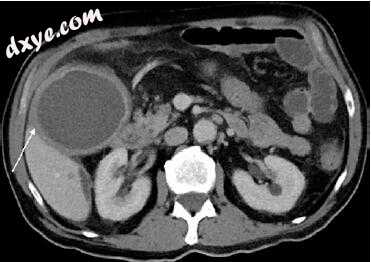

图5.6 69岁女性女性慢性胆囊炎伴胆囊壁增厚(箭头),在门静脉期CT增强成像中无实质性包绕胆囊周围无结石的胆囊